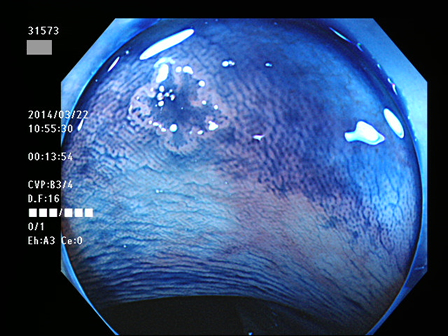

上記100名より抽出した平坦・陥凹型腺腫(=癌化の危険が高いが見落としやすい病変)の内視鏡写真

31532 31533 31534(SSA/Pのみ) 31537 31538 31539 31540 31541 31542 31545 31546 31550 31552 31553 31554 31555 31556 31562(SSA/Pのみ) 31563 31564 31565 31566 31567 31572 31573 31574 31576 31578 31579 31580 31581 31582 31586 31587 31589 31590 31591 31593 31596 31597 31598 31599 ・・・・の65名